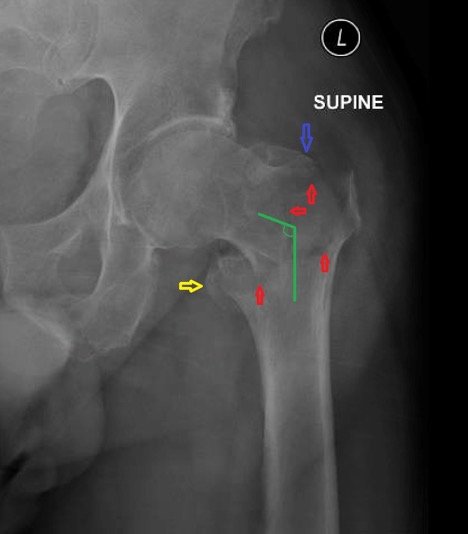

2. Intertrochanteric fractures

Located between the greater and lesser trochanters, these fractures occur just outside the hip joint capsule.

- Generally more stable than intracapsular fractures

- Often treated with internal fixation using a rod or plate and screws

- Can occur from falls in older adults or high-impact trauma in younger people